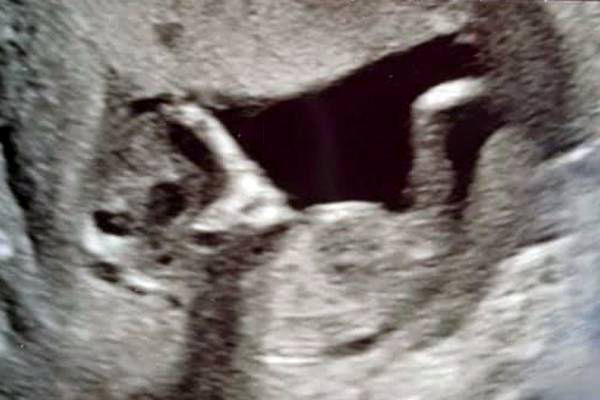

چشمان ترسناک یک جنین در شکم مادرش/ زن جوان شوکه شد! + عکس

سونوگرافی ترسناک یک زوج انگلیسی در فضای مجازی خبرساز شد.

همسرم وقتی نوزاد را دید بسیار متعجب شد و تا چند دقیقه فقط به او خیره شده بود...